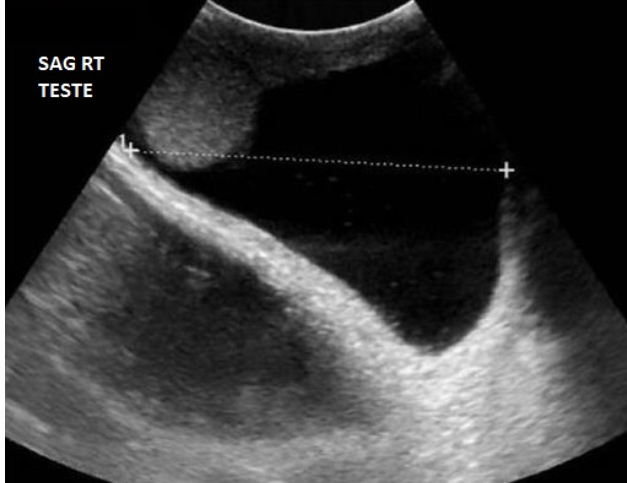

Which measurement on the hydrocele is being assessed on the image?

A) length

B) AP

C) width

Why?

The image is a Sagittal view which means the calipers are measuring the superior to inferior dimension AKA length.